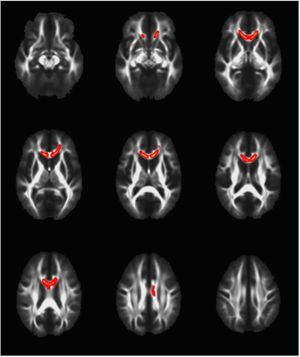

Potential of Diffusion Tensor Imaging and Relaxometry for the Detection of Specific Pathological Alterations in Parkinson's Disease (PD)

Publication: PLoS One. 2015 Dec 29;10(12):e0145493. PMID: 26713760 | PDF Authors: Esterhammer R, Seppi K, Reiter E, Pinter B, Mueller C, Kremser C, Zitzelsberger T, Nocker M, Scherfler C, Poewe W, Schocke M. Institution: Department of Radiology, University Hospital, Innsbruck Medical University, Innsbruck, Austria. Background/Purpose: The purpose of the present study was to evaluate the potential of multimodal MR imaging including mean diffusivity (MD), fractional anisotropy (FA), relaxation rates R2 and R2* to detect disease specific alterations in Parkinson's Disease (PD). We enrolled 82 PD patients (PD-all) with varying disease durations (≤5 years: PD≤5, n = 43; >5 years: PD>5, n = 39) and 38 matched healthy controls (HC), receiving diffusion tensor imaging as well as R2 and R2* relaxometry calculated from multi-echo T2*-weighted and dual-echo TSE imaging, respectively. ROIs were drawn to delineate caudate nucleus (CN), putamen (PU), globus pallidus (GP) and substantia nigra (SN) on the co-registered maps. The SN was divided in 3 descending levels (SL 1-3). The most significant parameters were used for a flexible discrimination analysis (FDA) in a training collective consisting of 25 randomized subjects from each group in order to predict the classification of remaining subjects. PD-all showed significant increases in MD, R2 and R2* within SN and its subregions as well as in MD and R2* within different basal ganglia regions. Compared to the HC group, the PD≤5 and the PD>5 group showed significant MD increases within the SN and its lower two subregions, while the PD≤5 group exhibited significant increases in R2 and R2* within SN and its subregions, and tended to elevation within the basal ganglia. The PD>5 group had significantly increased MD in PU and GP, whereas the PD≤5 group presented normal MD within the basal ganglia. FDA achieved right classification in 84% of study participants. Micro-structural damage affects primarily the SN of PD patients and in later disease stages the basal ganglia. Iron contents of PU, GP and SN are increased at early disease stages of PD. Funding:

The regions-of-interest (ROIs) were manually drawn by an experienced radiologist by using the b 1000 images, averaged for all measured directions, the FA maps and the proton-density weighted images. For that purpose, the maps of ADC, FA, R2 and R2* as well as the proton-density weighted images were first co-registered. The ROIs were segmented by syncing the b 1000 images, averaged for all measured directions, the FA maps and the proton-density weighted images in ImageJ. The ROIs were stored in the ROI manager and transferred to the co-registered maps. The segmented brain regions were highlighted in different colors: CN—black; PU—red; GP—green; TH—white; SN—blue; CC—cyan. The diffusion-weighted images, the R2 and R2*-weighted maps were transferred to the 3D Slicer software in order to co-register the R2 and the R2* maps as well as the MD and the FA maps |